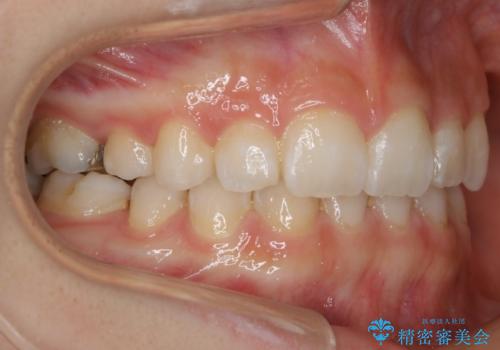

- 歯のガタつきを主訴にご来院されました。

ガタつきがあるだけでなく、元々永久歯が欠損している「先天欠如」で歯の本数が少なく噛み合わせ等も治療する必要がありました。

かなり特殊な状況からの矯正治療になるため抜歯する本数や位置、並んだあとのスペースのコントロールを慎重に計画し、マウスピース装置のインビザラインで治療を開始しました。